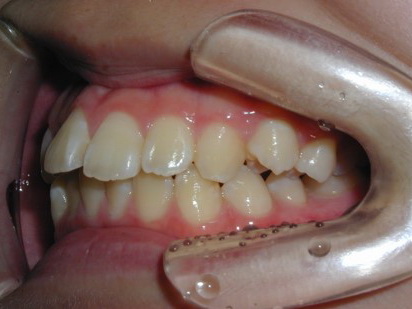

永久歯に交換するためのスペース不足による前歯のガタガタで、取り外しができる拡大床にて上下顎の幅を拡大した後、上顎の前歯をマルチブラケット装置で並べました。治療の期間は1年9か月でした。

初診時